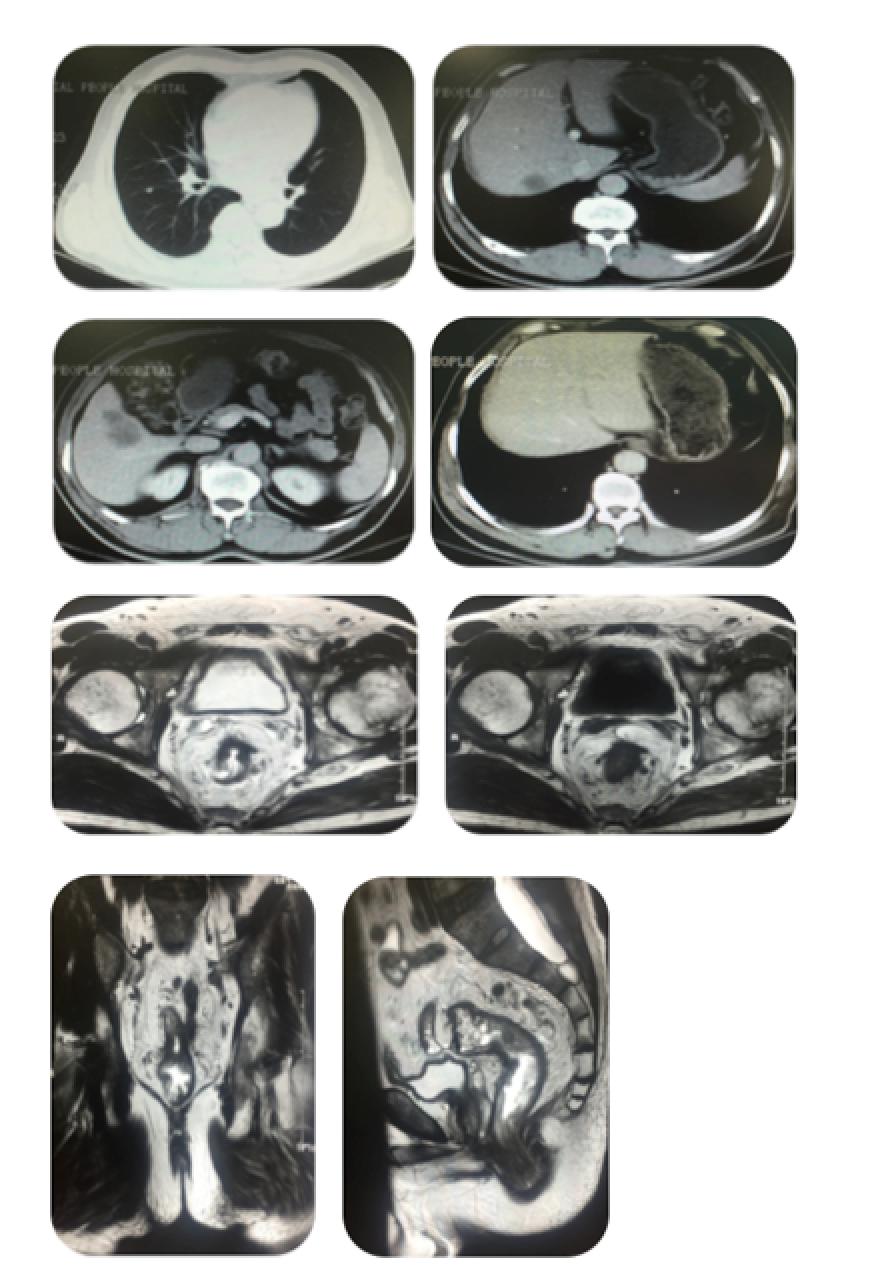

入院时胸、腹、盆腔等影像学检查及CT/MRI片子

胸部CT:右肺下叶小结节

上腹部增强CT:肝内多发低密度影 (较大者4.8*4.5cm)

盆腔增强CT :1.直肠壁不规则增厚;2.盆腔及双侧腹股沟多发淋巴结,部分轻度肿大;3.右侧髂骨内结节状高密度影;4.左侧髋关节退行性变;

2015-8 胸部、上腹部及盆腔CT

2015-8上腹部增强CT: